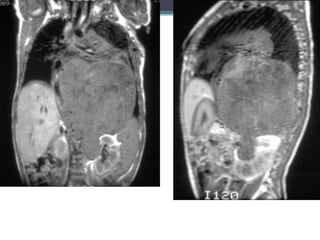

MRI exam performed 3 weeks after

diagnosis. Coronal and sagittal T1

weighted images without contrast, and

coronal and axial T2 weighted MRI

images could not definitely identify the

left adrenal gland, and therefore

suggested it could be the origin of the

midline mass. There was evidence of

tumor invasion into several neural

foramina and the spinal canal.

Dx-Neuroblastoma